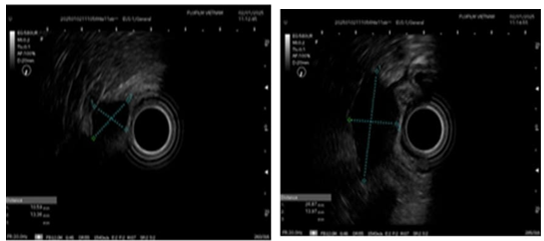

Nội soi siêu âm: Sử dụng đầu dò Radial đánh giá 2 tổn thương dưới niêm mạc mặt trước thân vị dạ dày: 2 tổn thương giảm âm không đều, thuộc lớp cơ thành dạ dày, kích thước khoảng 1.5 cm và 2.8 cm. Các lớp còn lại của dạ dày không thấy bất thường, không thấy hạch xung quanh.

Hình 3. Hình ảnh nội soi siêu âm 2 tổn thương giảm âm không đều, thuộc lớp cơ thành dạ dày, kích thước 1.5 cm và 2.8 cm.